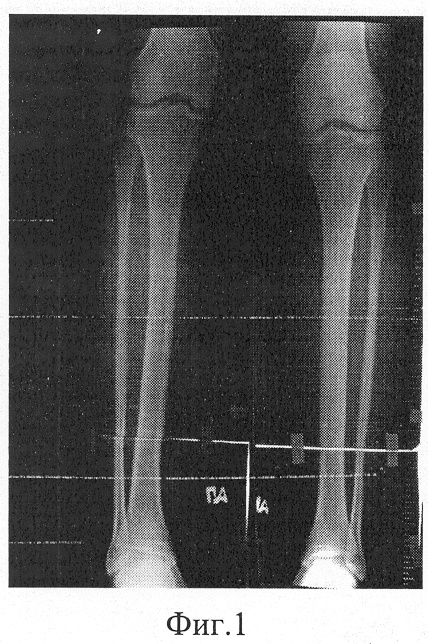

фиг.1 – фоторентгенограмма голеней больного до лечения;

Больной К., 20 лет, поступил в клинику ГУ РНЦ “ВТО” им. акад. Г.А.Илизарова с диагнозом: субъективно низкий рост.

Для увеличения продольных размеров голеней больному выполнена операция: остеотомия берцовых костей; остеосинтез аппаратом Илизарова.

В ходе операции для фиксации фрагментов берцовых костей чрескостно перекрестие провели по четыре спицы через проксимальный и дистальный метаэпифизы берцовых костей и две – через среднюю часть их диафиза. В натянутом состоянии спицы закрепили на внешних опорах аппарата, которые соединили между собой с возможностью дозированного, разноплоскостного перемещения с помощью резьбовых стержней и шарнирных узлов. Остеотомию берцовых костей выполнили через разрезы мягких тканей в проксимальных отделах голеней.